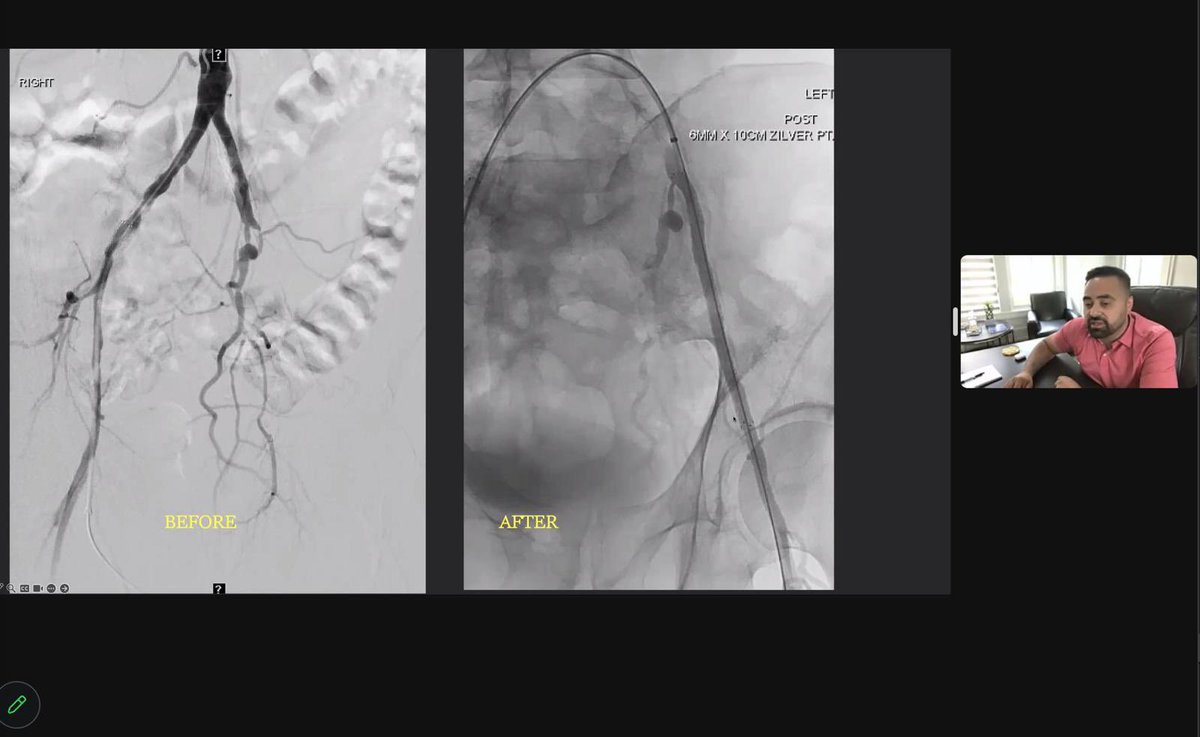

Spot the anatomical variant . #irad #cardiovascular #MedEd #MedTwitter #medx #radtwitter #vascular #radres #radiology Society of Interventional Radiology BSIR Trainees (British Society of IR Trainees) SIR RFS SIR ECS Interventional Radiology BIR, RGGGH@Chennai Radiology AppliedRadiology RSNA Amar Udare, MD - RadioGyan.com KDAH Radiology Sandeep Awal | RadiologyVibes.com Lea Alhilali, MD